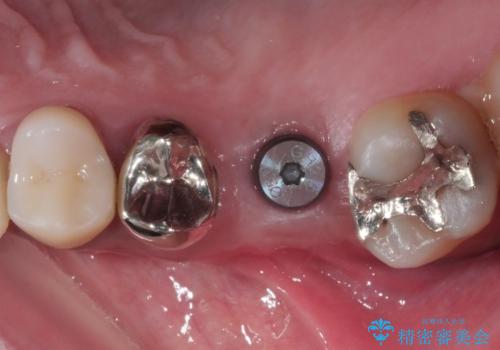

レントゲン等、検査を行ったところ骨の厚みは問題ないですが、

高さは少し低かったので、幅が太い短いインプラントを使って治療を行う計画を立てました。